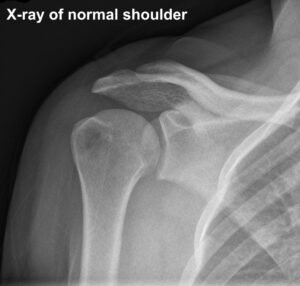

The shoulder joint is a ball and socket type of joint between the head of humerus (ball) and glenoid (socket). Shoulder dislocation is when the head of humerus (ball) completely pops out of the cup-shaped socket (glenoid). If it happens partially it is called subluxation.